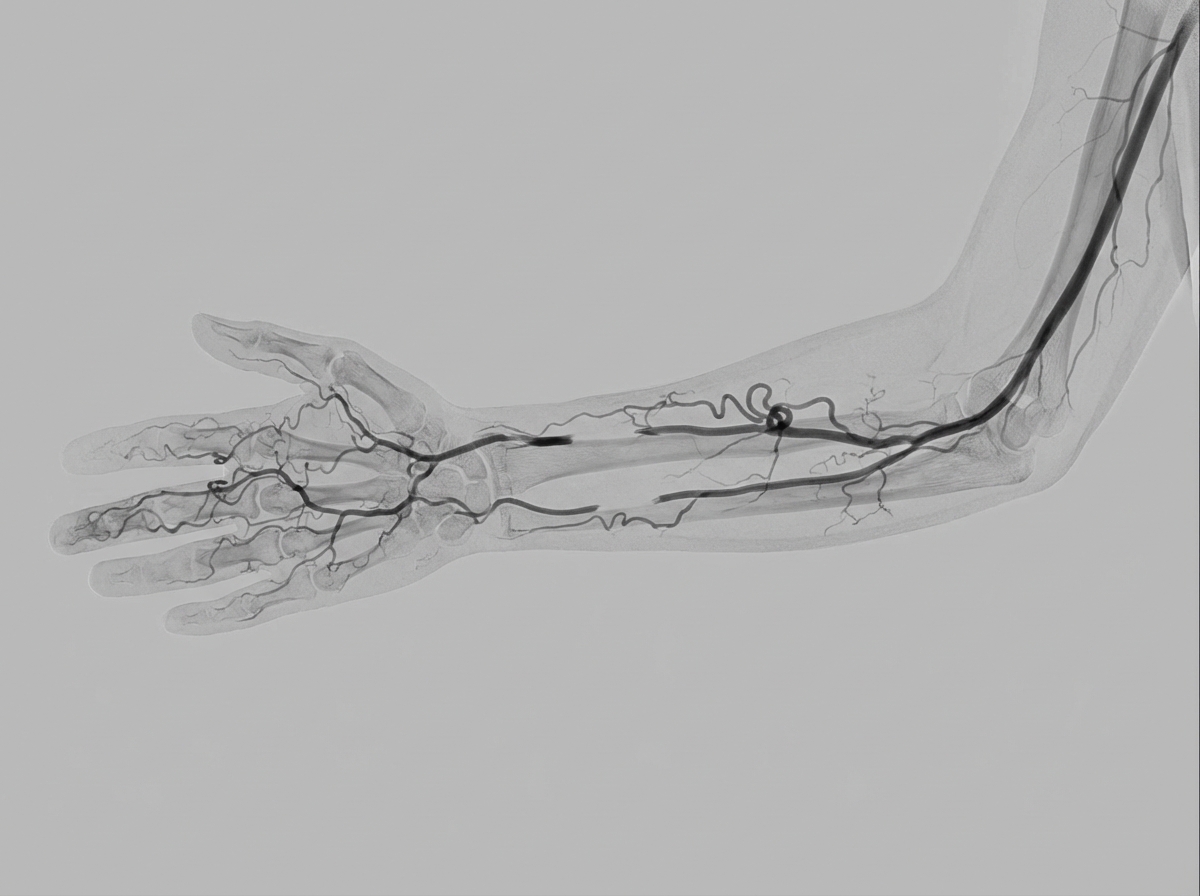

A 30-year-old construction worker presented with exertional pain in his bilateral forearms and hands. There is a history of chronic cigarette smoking. On examination, faint radial and ulnar pulses were noted, with easily palpable brachial pulses. Angiography of the hand was performed. Which of the following is the best treatment for this condition?

Explanation: ***Smoking cessation*** - This is **Buerger's disease** (thromboangiitis obliterans), a condition almost exclusively seen in **young male smokers** with distal limb ischemia. - **Smoking cessation** is the only definitive treatment that can halt disease progression and prevent further vascular occlusion, as continued smoking leads to irreversible vessel damage. *Enoxaparin* - **Low molecular weight heparin** is not effective in Buerger's disease as this is primarily an **inflammatory vasculitis** rather than a thrombotic condition. - The pathophysiology involves **segmental inflammation** of small and medium arteries, not typical thromboembolic disease requiring anticoagulation. *Prednisolone* - **Corticosteroids** have limited efficacy in Buerger's disease and are not considered first-line treatment. - While inflammation is present, the primary driver is **tobacco use**, and immunosuppression does not address the underlying cause or significantly improve outcomes. *Warfarin* - **Oral anticoagulation** is ineffective in treating the underlying **thromboangiitis obliterans** pathology. - The characteristic **corkscrew collaterals** and **segmental vessel occlusion** seen on angiography are due to inflammatory vessel wall changes, not embolic phenomena requiring anticoagulation.